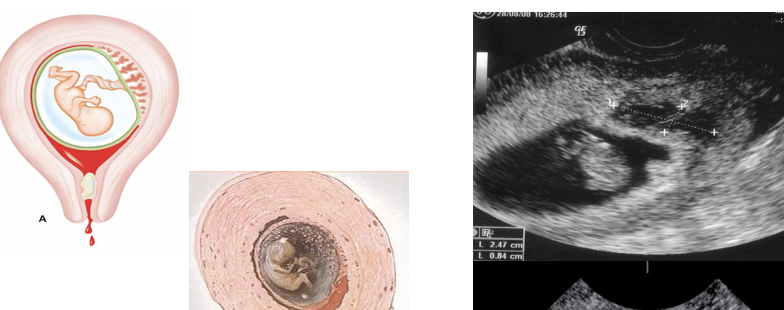

• Embarazo ectópico

• Enfermedad trofoblástica gestacional

2